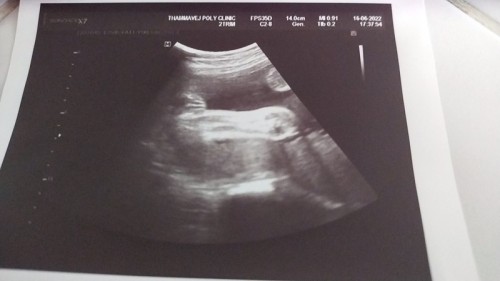

ซาวด์28วิคหมอบอกเหมือนน้ำหนักน้องน้อยไปหน่อยท้องน้องเล็กขาน้องเล็กไปหน่อย เราต้องทานอาหารอะไรเพิ่งดี

เป็นเเบบลูกเราเลยหมอบอกน้องท้องเล็กเเขนขาน้อย ตอน32สัปดาซาวได้1700g 36สัปดา2000g คลอด40สัปดา ลูกได้2890 แต่ออกมาเเข็งแรงนะคะ แม่ครรภ์เป็นพิษตอนผ่า ช่วง36สัปดาคิดว่าต้องกินไห้ลงลูกเยอะๆตอนนั้นกินเเต่ใข่วันระ2-3 กับนมดีน่า ทุกรสเลย ใข่นมใข่นมจนคลอด ยังดีที่ลูกได้2890 (คุณแม่อย่าเครียดนะคะมีผลกับลูกในท้อง)

Đọc thêmเราก็เหมือนกันค่ะน้ำหนักแม่ลง แต่น้องไม่ลงคะกับจากหมอนัดเดือนมื่อกี้ เราไปหาหมอมามื่อวันที่22 ได้27wน้ำหนักน้องตอนนี้1200แล้วคะ เรากินผลไม้นมไข่ต้ม แล้วก็ทานของหวานเลยอะไปหน่อย🤣 โดยเฉพาะทุเรียนชอบมาก็อยากกินตลอดเลย

บ้านนี้ กินกับข้าวปกติค่ะ แต่ นมทุกวัน ไข่ต้มบางวัน กินครั้งนึงก็2-3ฟอง ข้าวโพดนึ่งบ้าง ผลไม้ทุกวัน แอปเปิ้ล ฝรั่ง สัปะรด หาหมอล่าสุด 26w นน.น้อง 1000กรัมค่ะ ส่วนแม่ นน.ขึ้น4กิโล ตอนนี้28w น้องดิ้นแรงดิ้นบ่อยมากค่ะ